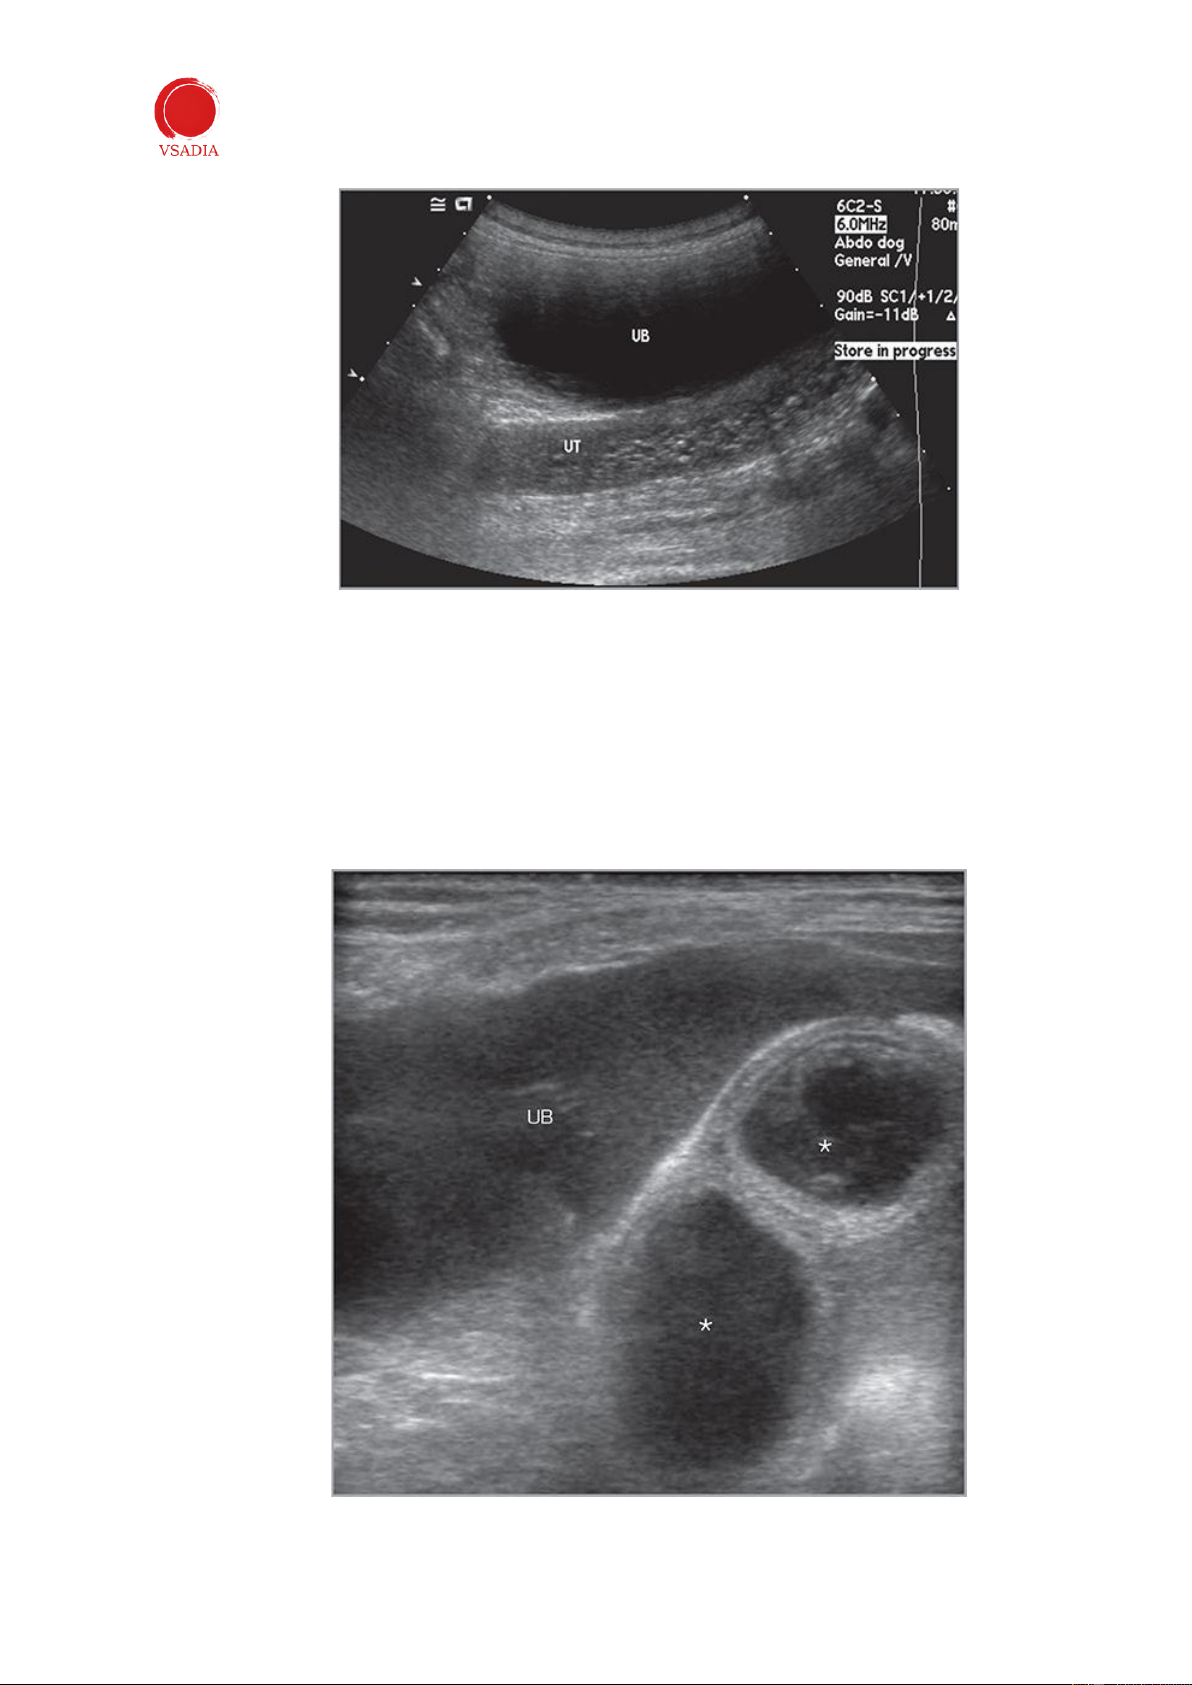

Tăng sản nội mạc tử cung dạng nang (CEH) thường xảy ra trước mủ tử cung và xuất

hiện trên siêu âm dưới dạng nội mạc tử cung dày lên chứa các cấu trúc nang không có tiếng vang (Hình 11).

Hình 11:Tăng sản nội mạc tử cung dạng nang . Thân tử cung (UT) có thể nhìn thấy được từ phía sau bàng

quang (UB). Nó có đường kính to hơn và thành tử cung chứa nhiều u nang nhỏ. -

Khi có mủ tử cung, tử cung và sừng tử cung to ra và chứa đầy dịch (Hình 12). Sự mở

rộng này thường đối xứng, mặc dù những thay đổi khu trú hoặc từng đoạn cũng có thể

được xác định. Nội dung tử cung có thể không có tiếng vang hoặc tiếng vang. Mủ tử

cung phải được phân biệt với niêm mạc, máu tích tụ và nước, có hình dạng siêu âm tương tự (Bảng 1).

Hình 12: Mủ tử cung ở một con chó. Tử cung (*) có vẻ giãn ra và chứa đầy dịch. UB: bàng quang tiết niệu.

Ở những con cái đã triệt sản, u hạt ở cuống tử cung xuất hiện dưới dạng một khối lớn (Hình 14).

Hình 14: (a) Hình ảnh cắt ngang của u hạt gốc tử cung (pyometra) ở chó. Có thể nhìn thấy gốc tử cung

giữa bàng quang và đại tràng. (b) Hình ảnh mặt cắt của mủ tử cung của một chú chó. Cuống tử cung

xuất hiện dưới dạng một khối hang tạo âm hỗn hợp ở phía sau bàng quang (UB). IV. Thai kỳ -